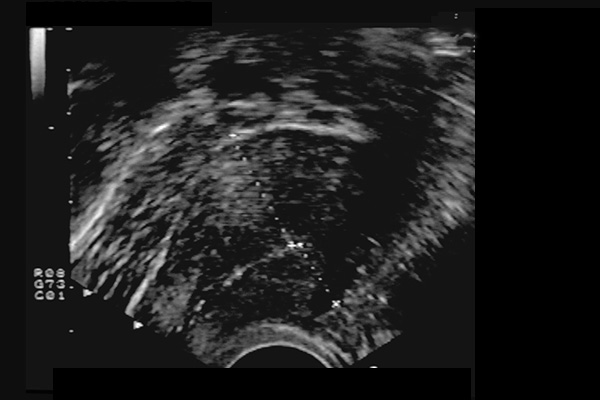

Adénomyose utérine. Paroi postérieure plus épaisse (BOHLMAN) - myomètre hétérogène vermoulu.